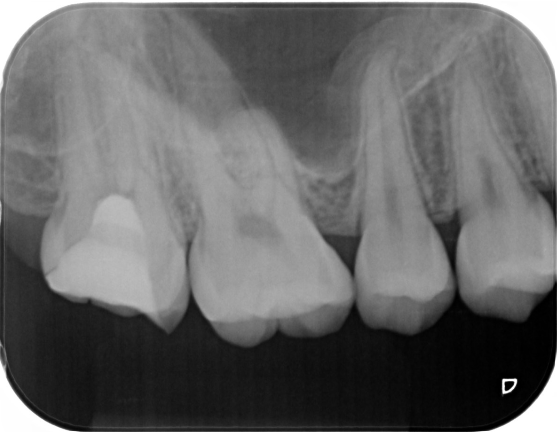

症例1

| 患者様データ | 13歳 女性 |

| 来院時の主訴 | 「右上奥歯が噛むと痛い。」 |

| 術前検査結果 | 歯髄の生活反応有り、自覚症状有り |

| 医院の診断 | 症候性可逆性歯髄炎 |

| ここがこだわりのポイント!☝ | 子供のうちは歯が口の中に生えてからも外からは見えない神経と歯根の成長は進んでいます。歯の成長期に神経をとってしまうとその成長が止まってしまうため、歯髄温存療法により神経の保存を試みました。結果、順調に歯は成長し、健康な大人の歯になることができました。MI治療が可能と判断したので、年齢も若いことから治療後は歯を極力削らない治療で終了しています。 |